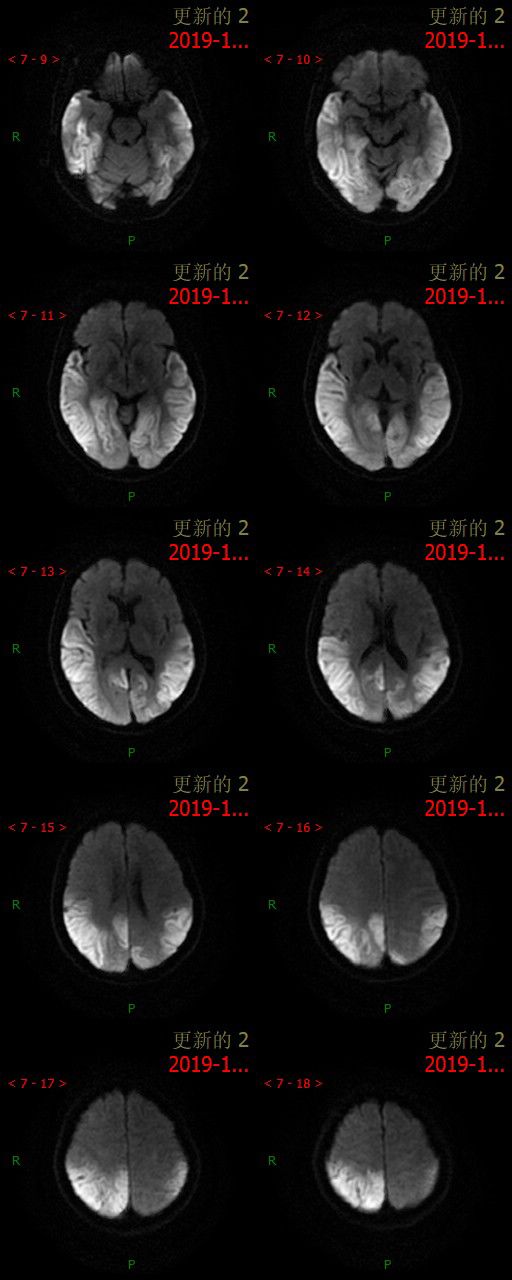

12.11 日 MR 平扫

患者为中年女性,临床症状不重,影像表现明显。双侧大脑半球多发病变,DWI 呈高信号,呈非对称性分布,且病灶分布呈跨血管支配区分布,DSA 为正常表现,可以排除脑梗死。短期内病灶迅速进展,MRS 可以看到明显倒置的乳酸双峰,考虑 MELAS。

①以大脑皮质灰质损害为主, 多累及半球后部颞顶枕叶,其次为颞叶、海马和海马旁回、额叶、小脑等,呈游走性、多变性、此起彼伏等表现;其特点是不按解剖血管分布, 累及皮质和皮质下白质, 可见皮质的层状异常信号;

②对称性双侧基底节、丘脑, 脑干等灰质核团损伤的异常信号;由于灰质核团的细胞代谢活动比白质纤维强, 容易受累;

③灰质和白质散在的异常信号;白质病变多侵犯较新的周围白质, 即皮质下和三角区后部白质。